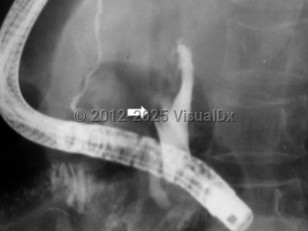

Ascaris lumbricoides is an intestinal parasite of humans and is the most common human helminthic infection worldwide, estimated to affect more than a billion people. Larvae and adult worms live in the small intestine of humans, and worm eggs are then passed in feces. Infection occurs when infective eggs are ingested, either from putting hands or fingers with contaminated dirt in the mouth or by eating contaminated fruits or vegetables that have not been sufficiently washed, peeled, or cooked. Outdoor defecation or the use of human feces as fertilizer can contaminate the soil with eggs. Eggs can remain viable through extreme temperatures and for several months in sewage.